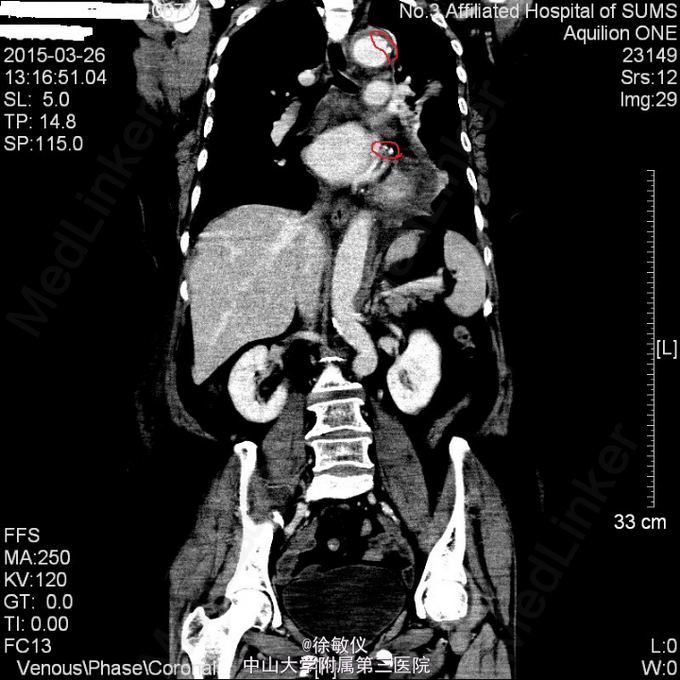

于急诊输液、止呕治疗后呕吐停止,胸闷持续3小时后症状减轻,予阿司匹林、氯吡格雷、立普妥负荷量口服后收入我科。 入院后查胸部、腹部ct发现有主动脉夹层。 诊断:冠状动脉粥样硬化性心脏病;主动脉夹层。

讨论:典型的急性主动脉夹层病人往往表现为突发的、剧烈的、胸背部、撕裂样疼痛。严重的可以出现心衰、晕厥、甚至突然死亡。该患者仅表现为胸闷,症状不典型。